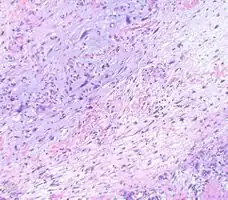

Myxofibrosarcoma-pathology -

Myxofibrosarcoma-pathology